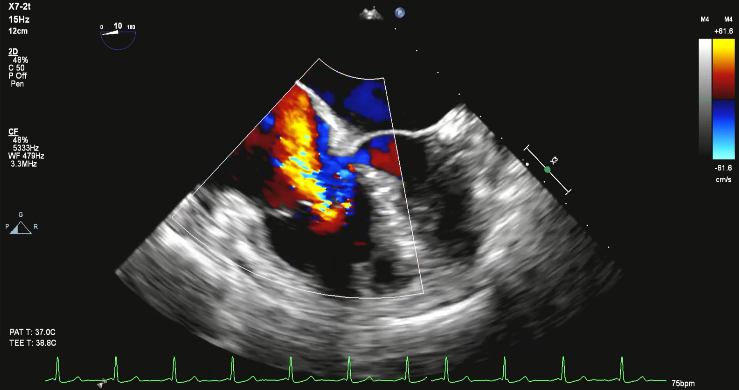

全麻下经右颈静脉入路,在食道超声及放射线引导下,将三尖瓣导丝输送导管经三尖瓣指引导管送至右心室,定位三尖瓣瓣环穿刺位点。穿越导丝连接高频发生器穿刺三尖瓣环(图2),在三尖瓣瓣环上植入一对锚片。通过缩短两个锚片之间的距离折叠三尖瓣瓣环,并通过3D-TEE、2D-TEE确认瓣环折叠及三尖瓣反流情况,最终实现三尖瓣瓣环的二瓣叶化(视频1),从而降低因瓣环扩大、瓣叶关闭不全产生的三尖瓣反流。

图2 :穿越导丝穿刺三尖瓣环(a:2D-TEE,b:3D-TEE)